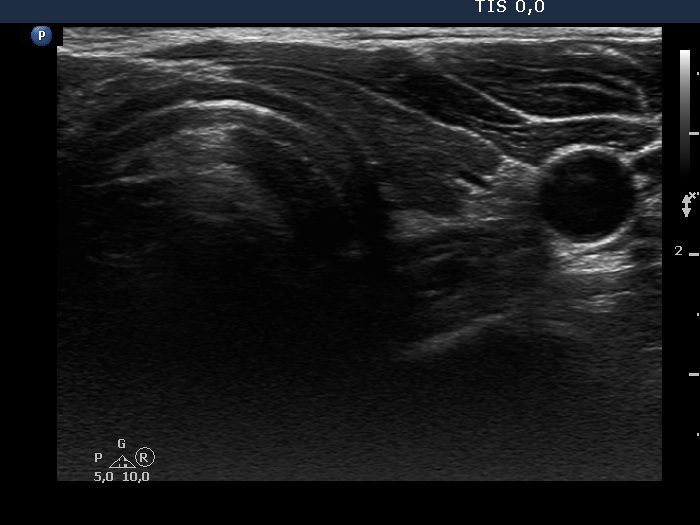

First examination (1st to 3rd rows of images):

Clinical presentation: A 47-year-old man was referred for evaluation of complaints suggesting subacute thyroiditis. He suffered from recurrent attacks of pain in the region of the thyroid radiating to the jaws. The pain was originally located to the left side of the neck but 2 weeks before the visit, both sides of the neck were affected. He had subfebrility, occasionally fever. He got 3 courses of antibiotics without any effect. The GP initiated investigation toward lymphoma of the neck.

Palpation: Both lobes were hard and painful.

Laboratory tests: euthyroidism with TSH-level 0.27 mIU/L, FT4 16.7 pM/L, CRP 35.1 mg/L, ESR 41 mm/H, aTPO 10 U/mL.

Ultrasonography: Both lobes presented hypoechogenic ill-defined areas. The echogenicity index was 80% in the right lobe while 20% in the left thyroid. The vascularization was significantly decreased.

Elastography demonstrated hard areas according to the hypoechogenic field in the left lobe while almost the entire right lobe proved to be hard.Cytological diagnosis: subacute, granulomatous de Quervain's thyroiditis.

Suggestion: steroid therapy was initiated and resulted in prompt amelioration of complaints.